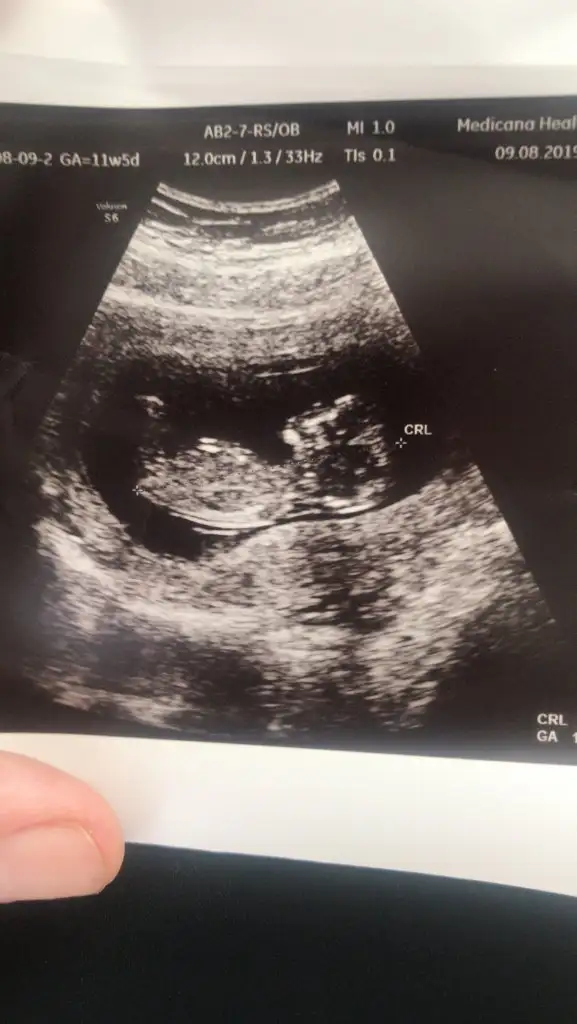

11+5 dr erken söylemiş saglıkla gelsin minoşunuz .Bu da teoriyi destekliyor mu bilmiyorum ama son ultrasonu. Yerinde durmuyor çiçeğimmm![]()

Evet ama ölçümde 12+4 çıktı tombulum11+5 dr erken söylemiş saglıkla gelsin minoşunuz .bende adanadan

Maşşallah minnoşaEvet ama ölçümde 12+4 çıktı tombulum![]()